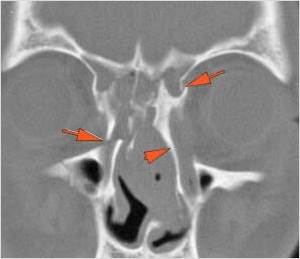

Fronto-Naso-Ethmoidal Complex

The mesial naso-orbito-ethmoid complex is fractured. Specifically, there is bony injury of the nasal bones or the frontal process of the maxilla and the medial walls of the orbit are abnormal.

The intercanthal distance is increased.

There is injury of the ethmoid complex. Specifically, the ethmoid roof, olfactory fossa and the cribriform plate are fractured and/or significantly dehiscent.